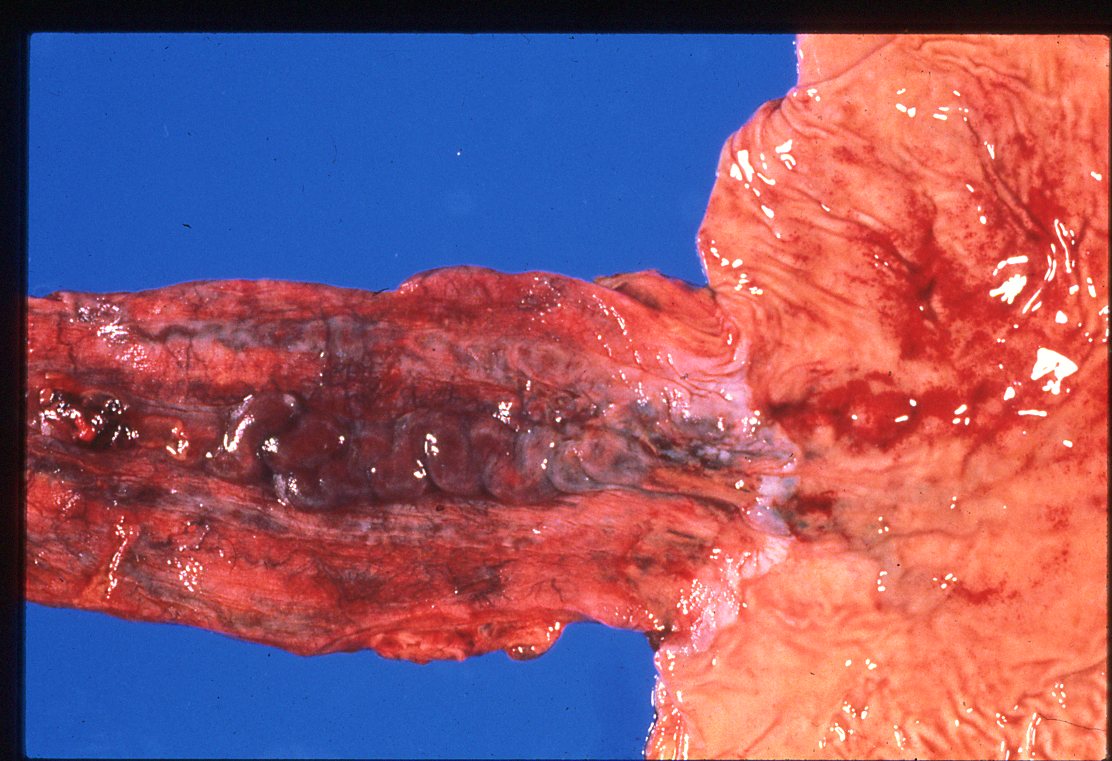

This image of esophageal varices is courtesy of Dr. Dale Snover. #UMiamiPath